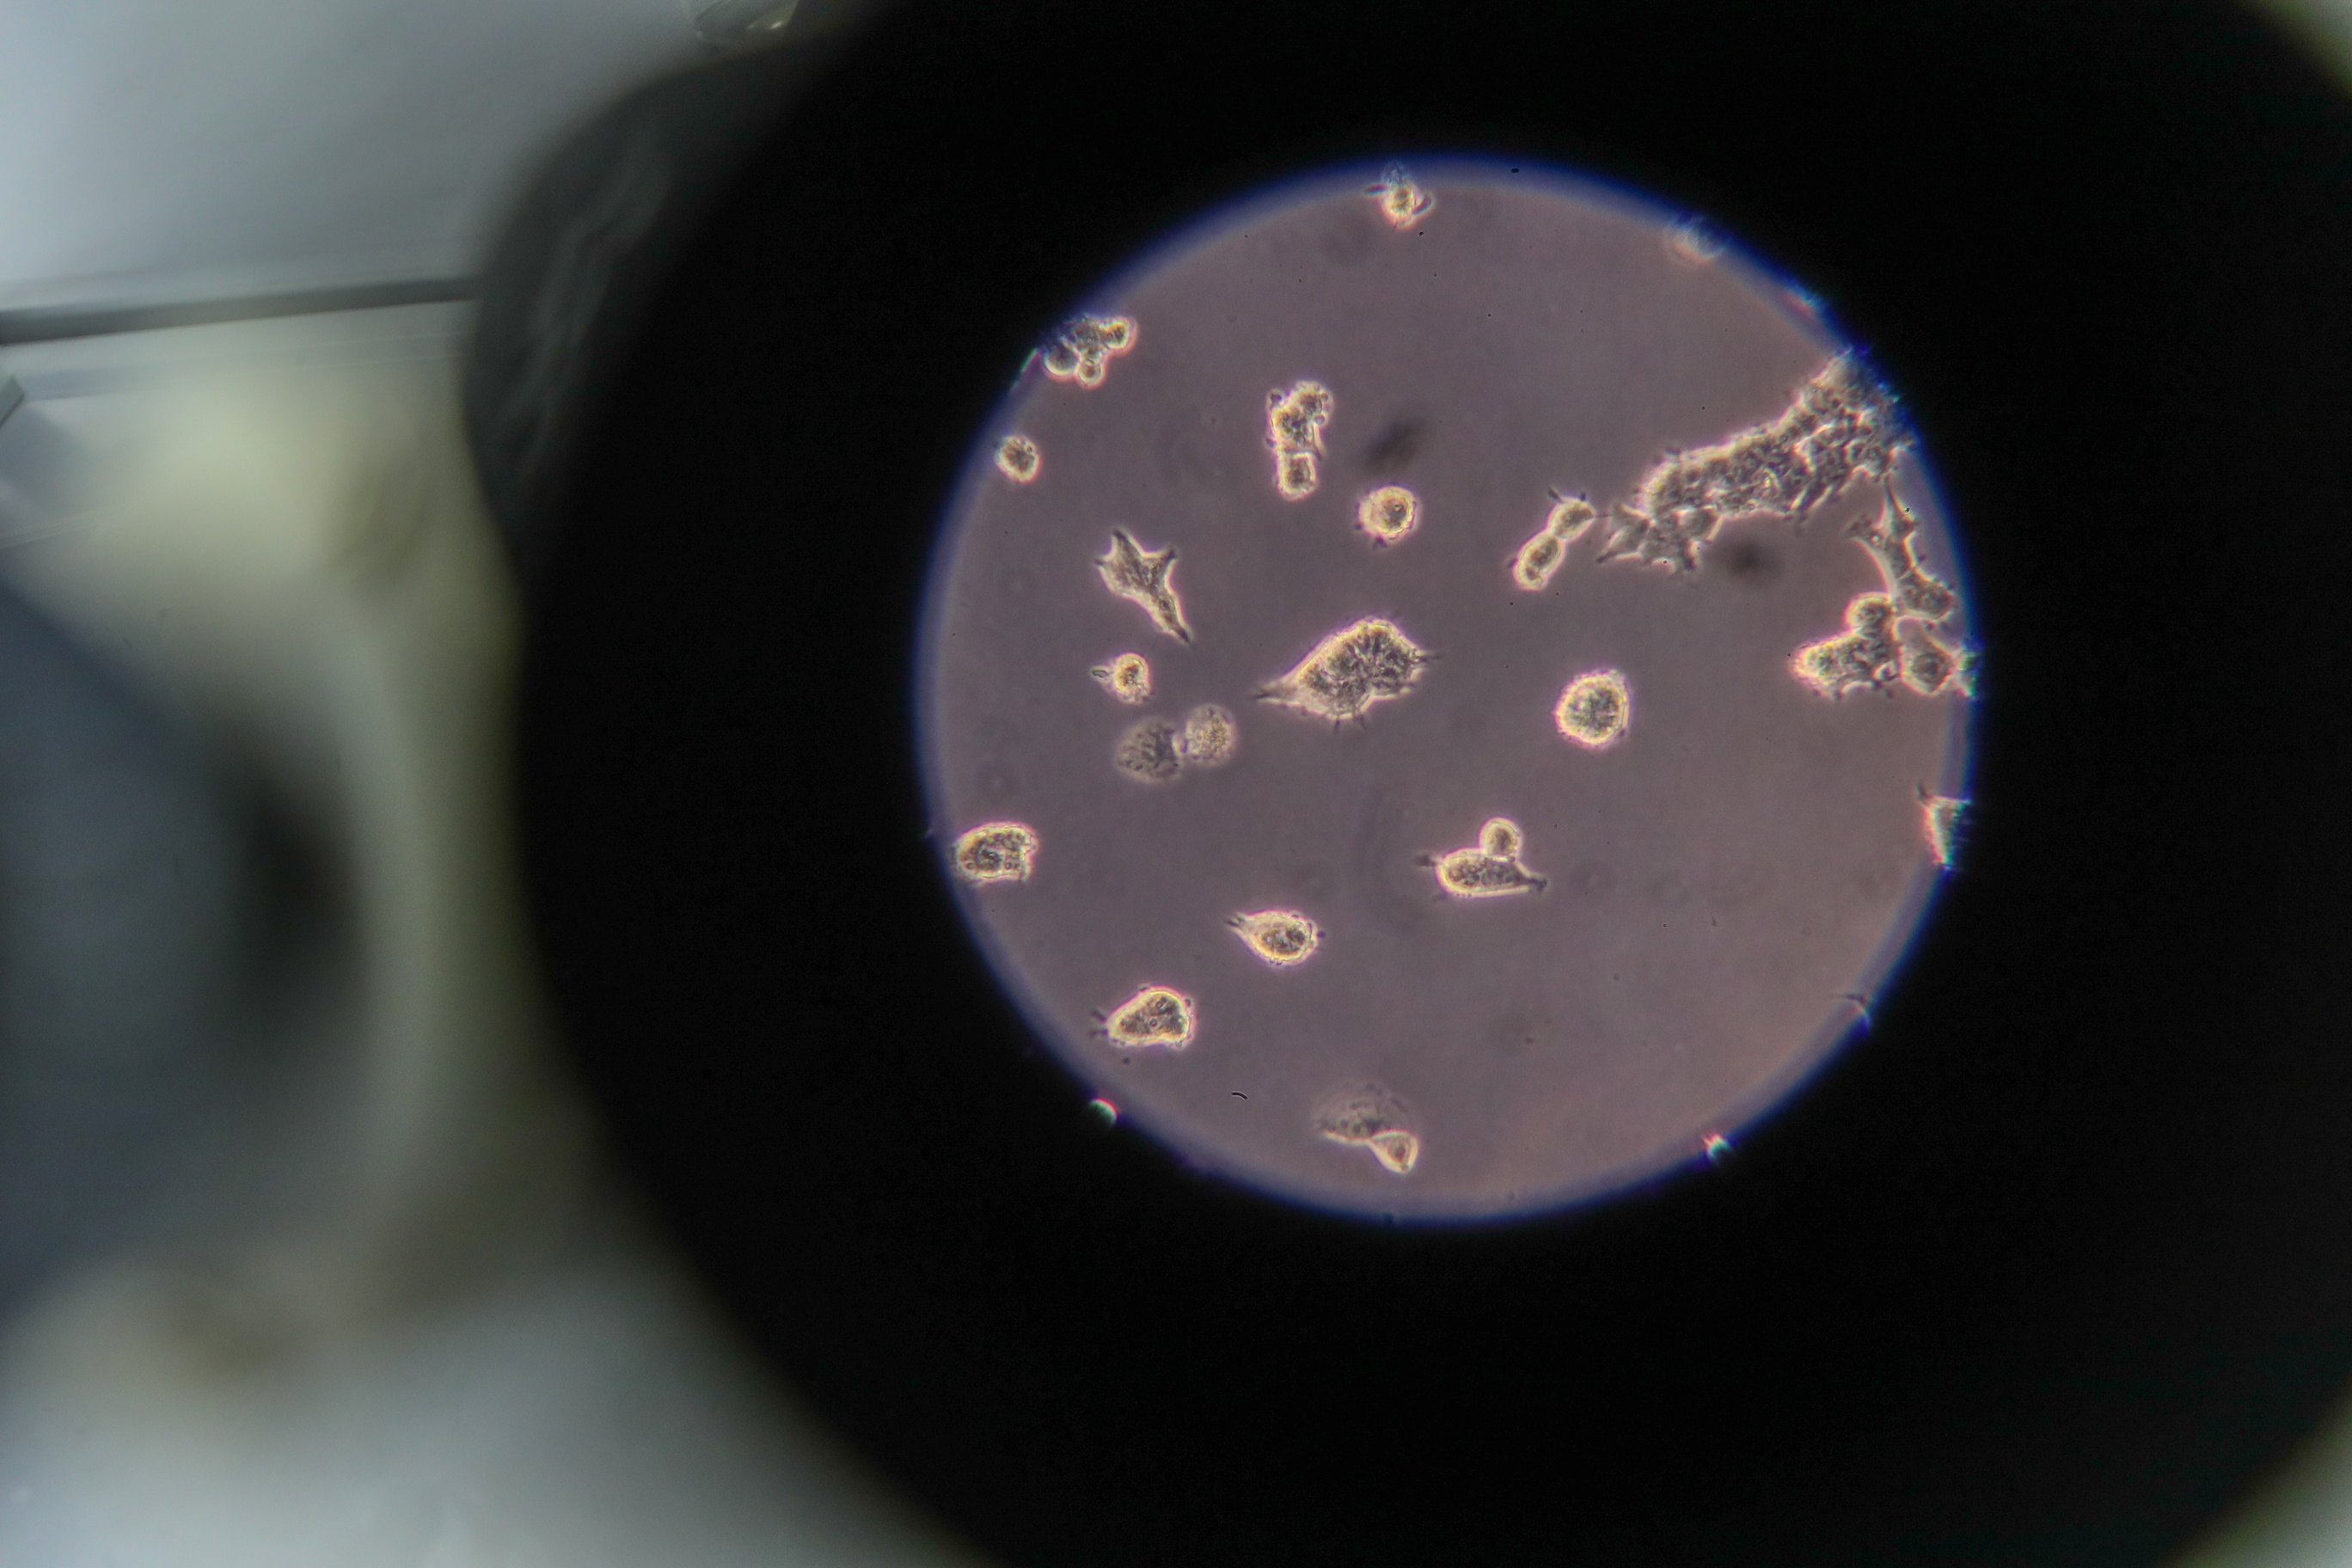

MOSCOW, April 20. /TASS/. A method to detect a full coronavirus genome and analyze its genetic variants developed by scientists of the Central Research Institute of Epidemiology of the Federal Service for Surveillance on Consumer Rights Protection and Human Wellbeing has allowed to isolate over 400 variants of SARS-CoV-2 with data published in Russian and foreign scientific databases, President of the Russian Academy of Sciences (RAS) Alexander Sergeyev told the general meeting of the Academy on Tuesday.

"A method for detection of full sequences of genomes and analysis of various gene variants was developed for epidemiological surveillance of COVID-19. A primer model was developed which allows to identify a full genome using only 17 pairs of primers. <…> Now <…> more than 400 genomes of SARS-CoV-2 have been defined, 300 of them were published in the domestic database and 270 - in the international one," the Academy’s president said.